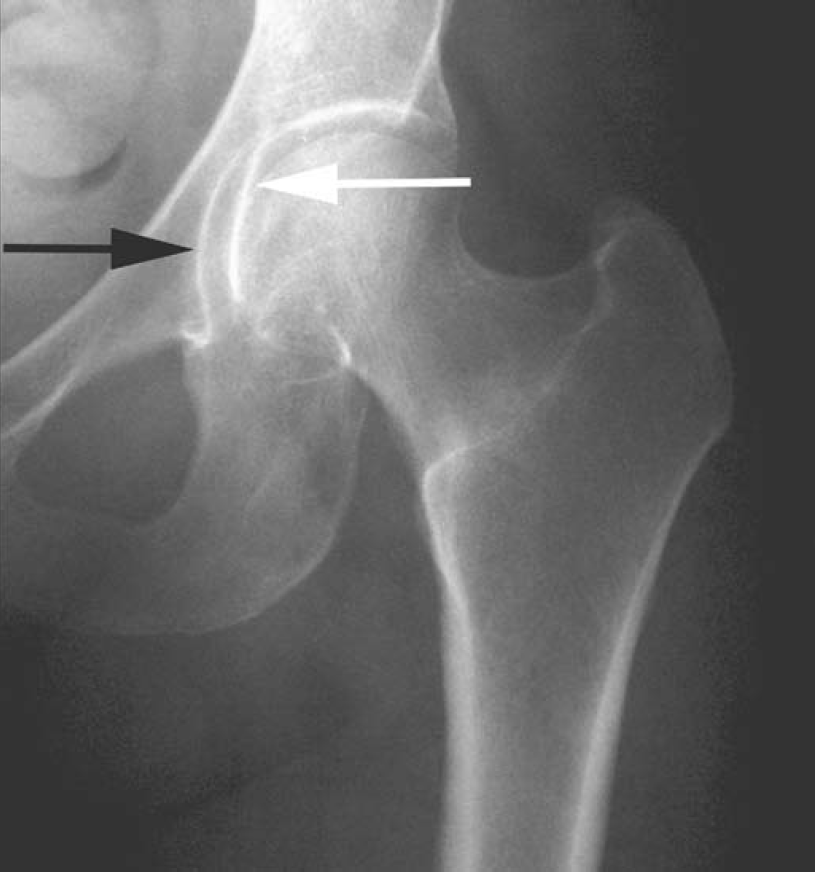

髓关节撞击综合征(femoroacetabular-impingement,FAI)是引起髋关节疼痛及髋关节进行性退行性变的一种常见病因。一般采用骨盆X线前后位照片筛查。骨盆照片时X线中心线应对准尾骨中心及耻骨联合,以保证骨盆不旋转。FAI主要分为3种类型:凸轮型、钳型和混合型。混合型FAI同时具有凸轮型和钳型的异常。凸轮型是股骨头颈连接处形成/发育异常所致,表现为股骨头颈连接处骨性隆起或“枪柄样”改变(缺乏正常的凹度)(图1)。钳型FAI表现为髋臼覆盖或位置异常,可根据在X线平片上见到深髋臼、髋臼前突或髋臼后倾的表现而诊断。深髋臼及髋臼前突X线表现为股骨头及髋臼相对髂骨坐骨线位置异常(图2)。髋臼后倾表现为交叉征、髋臼后壁征、坐骨棘突出征(图3)。

图2 32岁女性,左髋关节疼痛

骨盆前后位X线片局部截图,显示左髋关节。深髋臼表现为髋臼(黑箭)投影于髂骨-坐骨连线(白箭)内侧。深髋臼可导致钳型FAI